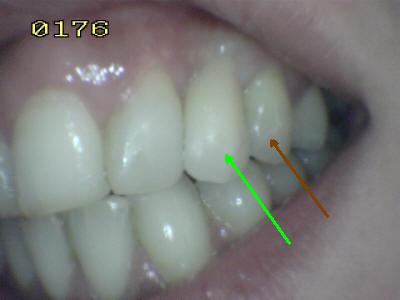

Prueba  de la porcelana  El matiz del póntico (flecha verde) se determino con el primer premolar (flecha marrón); en palatino se observa el contacto dentario antagonista en oclusión habitual. Note como el brazo palatino del retenedor envuelve casi toda la cara palatina; el ideal  es que sea mayor a 180º ; para lograr una máxima retención y estabilidad

Vista vestibular. El matiz del póntico (flecha verde) se determino con el primer premolar (flecha marrón) Antes del tratamiento